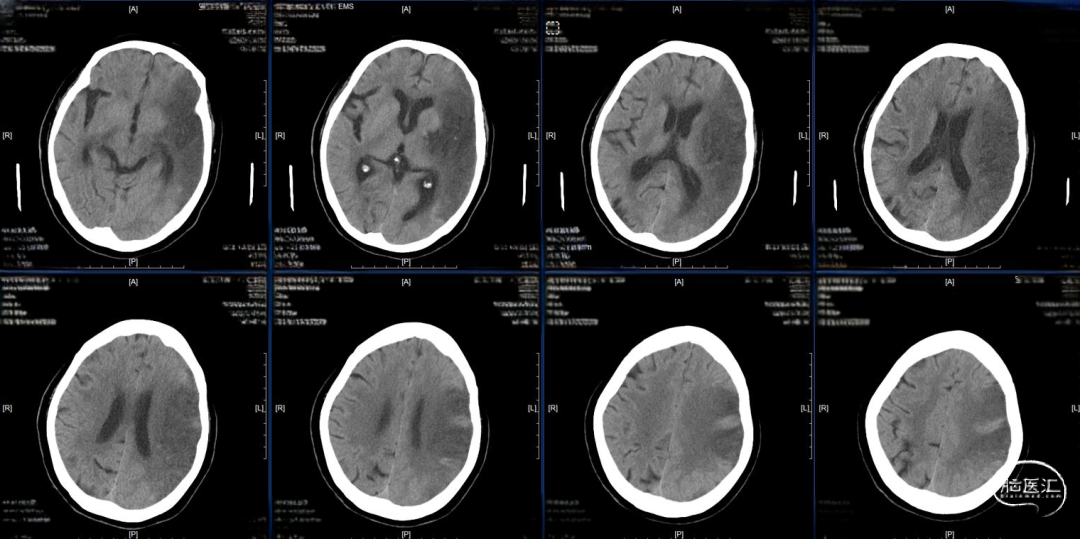

术后24小时复查CT,高灌注、轻肿胀,未见明显出血,轻度镇静至停用镇静,过程中可唤醒,自然复苏,呼吸机维持。

术后48小时复查CT,左半球大片低密度病灶、中线偏移,有主动睁眼、遵嘱动作,暂停呼吸机,延迟拔管,备去骨瓣。

术后96小时复查CT,左侧半球肿胀未继续进展,嗜睡,易唤醒、有睁眼、遵嘱动作,右侧肢体有自主动作,拔除气管插管。

术后第14天启动抗凝,术后第19天复查CT,术后第20天出院,NIHSS评分8分,mRs评分4分。